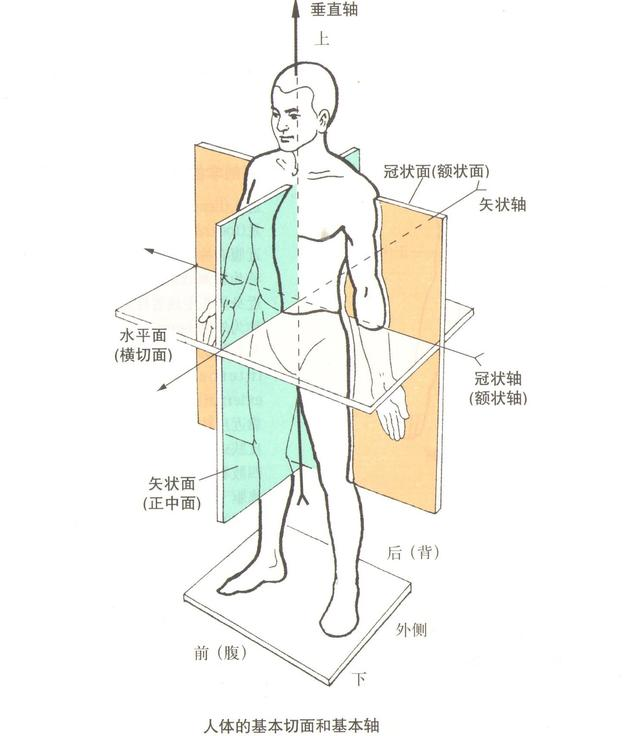

R-A-L-P-I-S" 是描述人体方位(解剖学方向)的一组首字母缩写,用于在医学影像(如 CT、MRI)或解剖学中精确标注身体的不同方向。每个字母代表一个方向:

R – Right(右)

A – Anterior(前)

L – Left(左)

P – Posterior(后)

I – Inferior(下)

S – Superior(上)

由此我们可以根据医学图像可视化软件ITK-SNAP中的标识识别每个窗口指向的切面